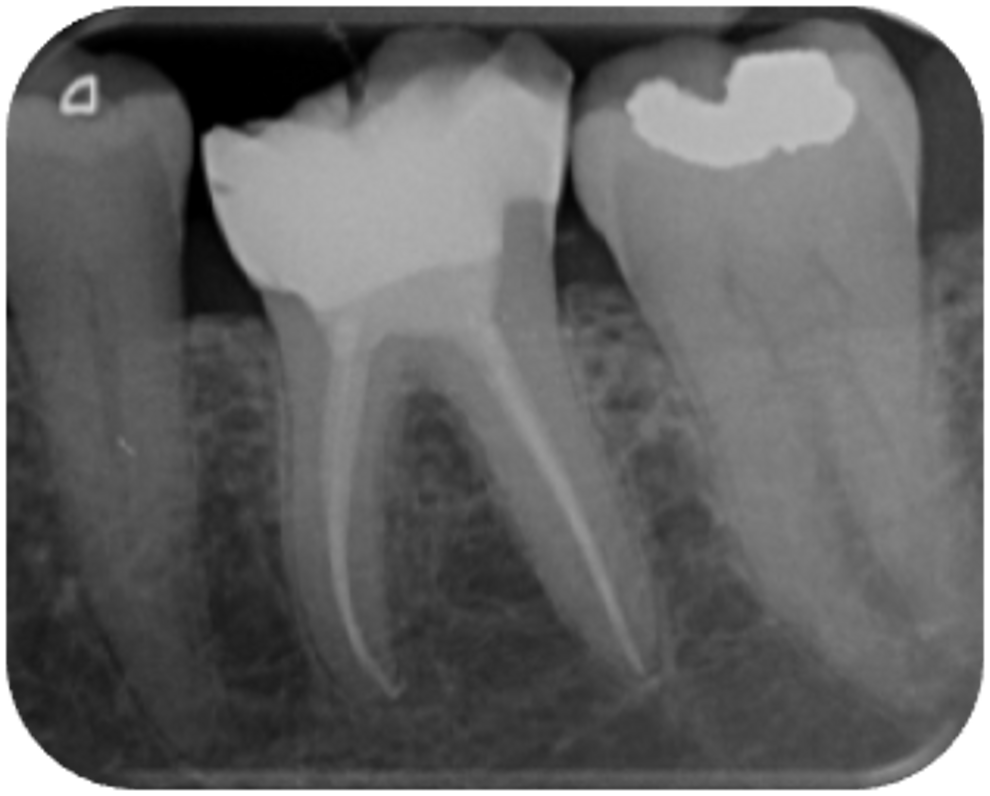

Extra-orally, no abnormality was detected. The intra-oral examination revealed an attempted extirpation; however, gross mesial caries had not been removed. The tooth mobility was Grade 0. The tooth was slightly tender to percussion, and there was mild buccal tenderness to palpation. There was no endodontic-related pocketing when the probe was walked around the gingival crevice. No evidence of a sinus tract or intra-oral swelling was found. A preoperative radiograph showed extensive mesial caries and a previous attempt at locating the canals. There was no obvious periapical pathosis radiographically (Fig. 1).

Fig. 1: Pre-op radiograph.